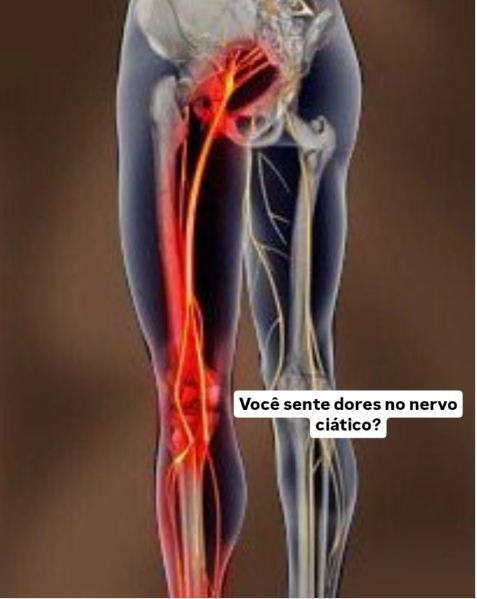

O nervo ciático é o maior nervo do corpo humano e percorre desde a região lombar até os pés. Quando há compressão ou tensão excessiva nos músculos e na fáscia — tecido que envolve e conecta as estruturas do corpo — podem surgir dores intensas, sensação de formigamento, queimação ou limitação de movimento.

A Liberação Miofascial atua diretamente nesses tecidos, utilizando pressões específicas e movimentos lentos para reduzir aderências, melhorar a mobilidade muscular e diminuir a compressão sobre o nervo. Durante o atendimento, são trabalhadas principalmente regiões como lombar, glúteos e parte posterior das pernas, áreas frequentemente relacionadas ao desconforto do ciático.